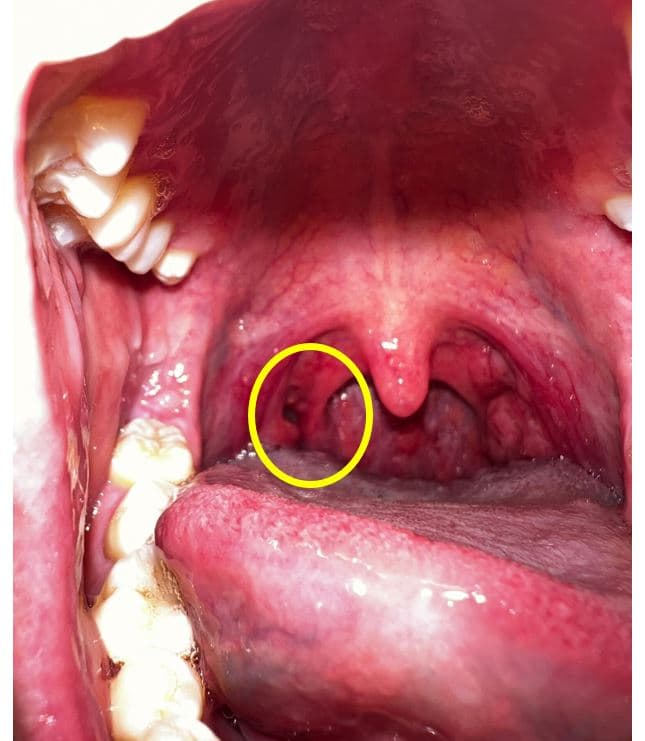

어느순간부터 편도쪽에 이질감과 함께 편도결석의 악취가 느껴져 핸드폰으로 촬영을 해봤습니다.

확인결과 목구명 편도 쪽에(아래사진의 목구멍편도 좌측 구멍) 구멍이 있습니다.

이상없을까요 ?

현재 병변은 구내염을 감별하는 것이 좋겠습니다.